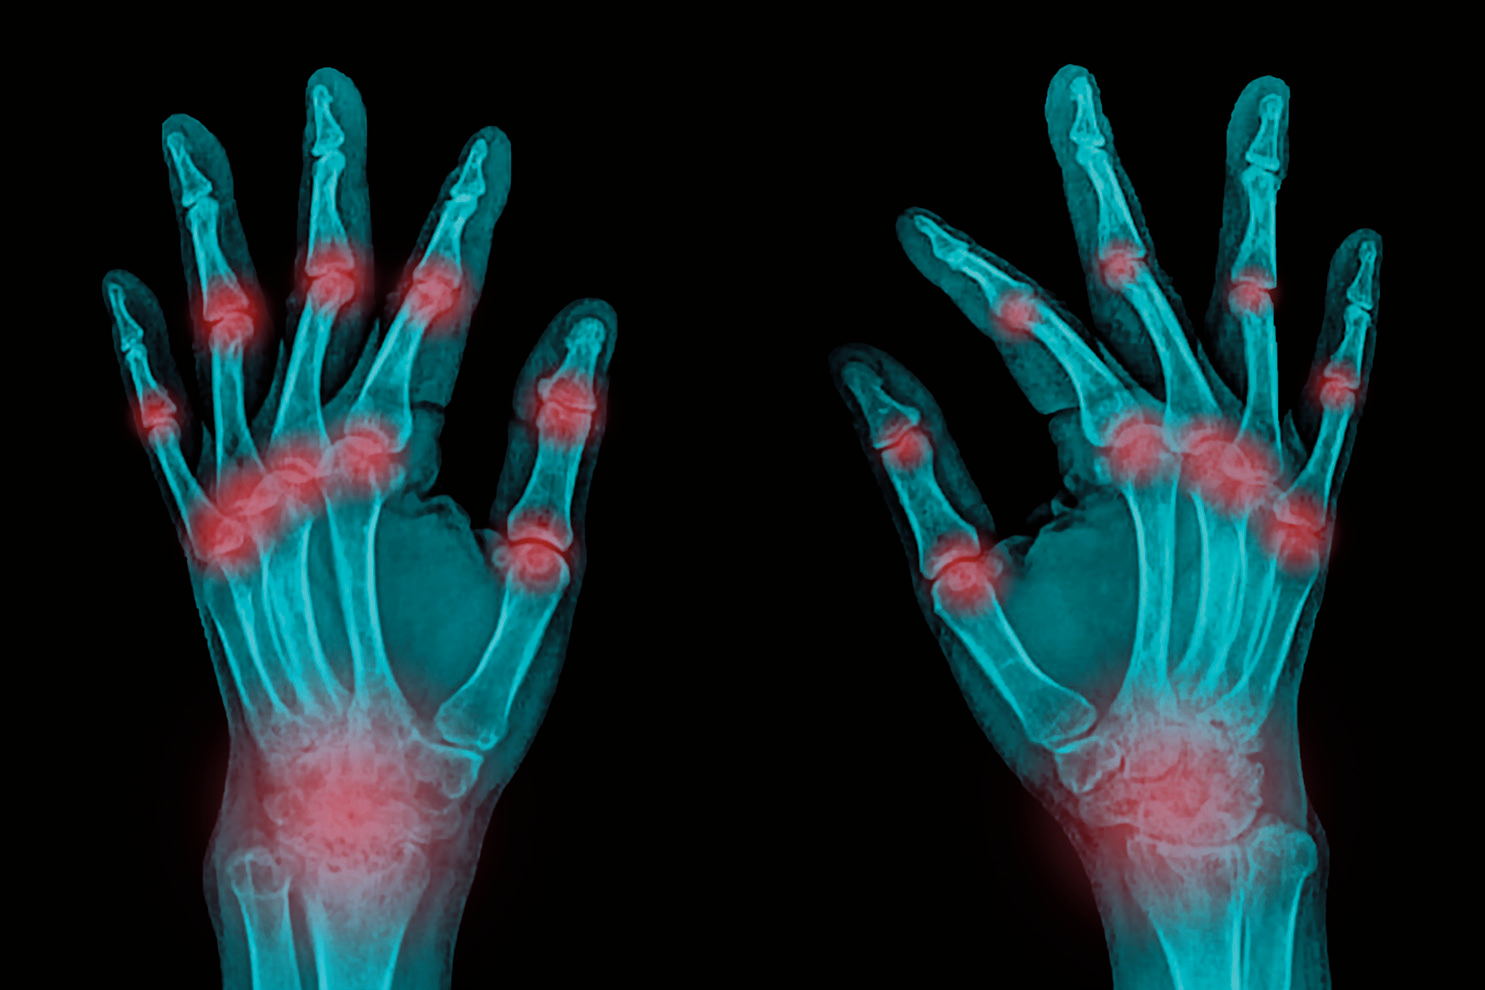

면역체계에 문제가 생겨 관절을 중심으로 인체 여러 기관에 염증이 일어나는 류마티스관절염은 완치가 불가능하다고 생각해 치료를 소홀히 하는 이들이 있다. 그러나 조기에 치료를 시작할수록 질병이 완전히 조절되는 관해 상태에 도달할 가능성이 높아진다.

퇴행성관절염과 달리 류마티스관절염은 면역체계에 문제가 생겨 면역세포가 관절내 활막을 공격해 염증이 일어나는 만성 염증성 질환으로, 관절뿐만 아니라 피부, 혈액, 침샘, 폐, 심장, 눈, 신경, 혈관 등에도 염증을 일으킬 수 있다.

아침에 자고 일어났을 때 손발에 뻣뻣한 느낌이 30분 이상 지속되고, 관절이 붓거나 아프면서 열감이 있다면 류마티스관절염을 의심해봐야 한다. 특히 손가락 관절, 발가락 관절, 손목, 발목, 팔꿈치, 무릎 등이 붓거나 아프고, 증상이 좌우 대칭적으로 나타나면서, 3군데 이상의 관절이 붓고, 이러한 증상이 6주 이상 이어지면 병원에서 검사와 정확한 진단을 받아보는 것이 좋다. 환자들은 주로 “관절이 아프고 붓는다” “아침에 손이 뻣뻣하다” “피곤하다” 등의 증상을 호소한다.

또한 퇴행성관절염은 노화 현상으로 관절의 연골이 닳아 없어지고 주위 뼈가 증식해서 생기는 비염증성 관절염이지만, 류마티스관절염은 면역체계의 이상으로 면역세포가 관절을 공격해 생기는 염증성 질환이다. 증상에도 차이가 있어서 퇴행성관절염은 손가락 끝마디가 딱딱하게 굵어지는 반면, 류마티스관절염은 손가락 중간마디나 중수지 관절, 손목관절 등에 증상이 주로 나타난다.

진단을 위해 혈액검사로 류마티스인자와 항CCP항체를 확인하고, X-ray 검사로 관절의 손상 여부를 살핀다. 그리고 ESR 과 CRP라는 염증 수치를 통해 염증 정도를 평가한다. 압통 관절과 종창 관절의 개수, 환자의 전반적인 건강 상태 점수, ESR과 CRP 수치 등을 수식에 대입해 계산하는 DAS28 질병 활성도 평가로 관절염이 얼마나 심한 상태인지를 파악한 뒤 치료 계획을 세운다.

류마티스관절염은 조기 진단으로 관절 손상을 최소화하는 것이 무엇보다 중요하다. 대한류마티스학회의 조사에 따르면 발병 2년 이내 환자의 52%, 1년 이내 환자의 21%에서 관절 손상이 관찰되었다. 관절 손상을 예방하려면 일반적으로 발병 6개월 이내에 치료를 시작해야 한다.